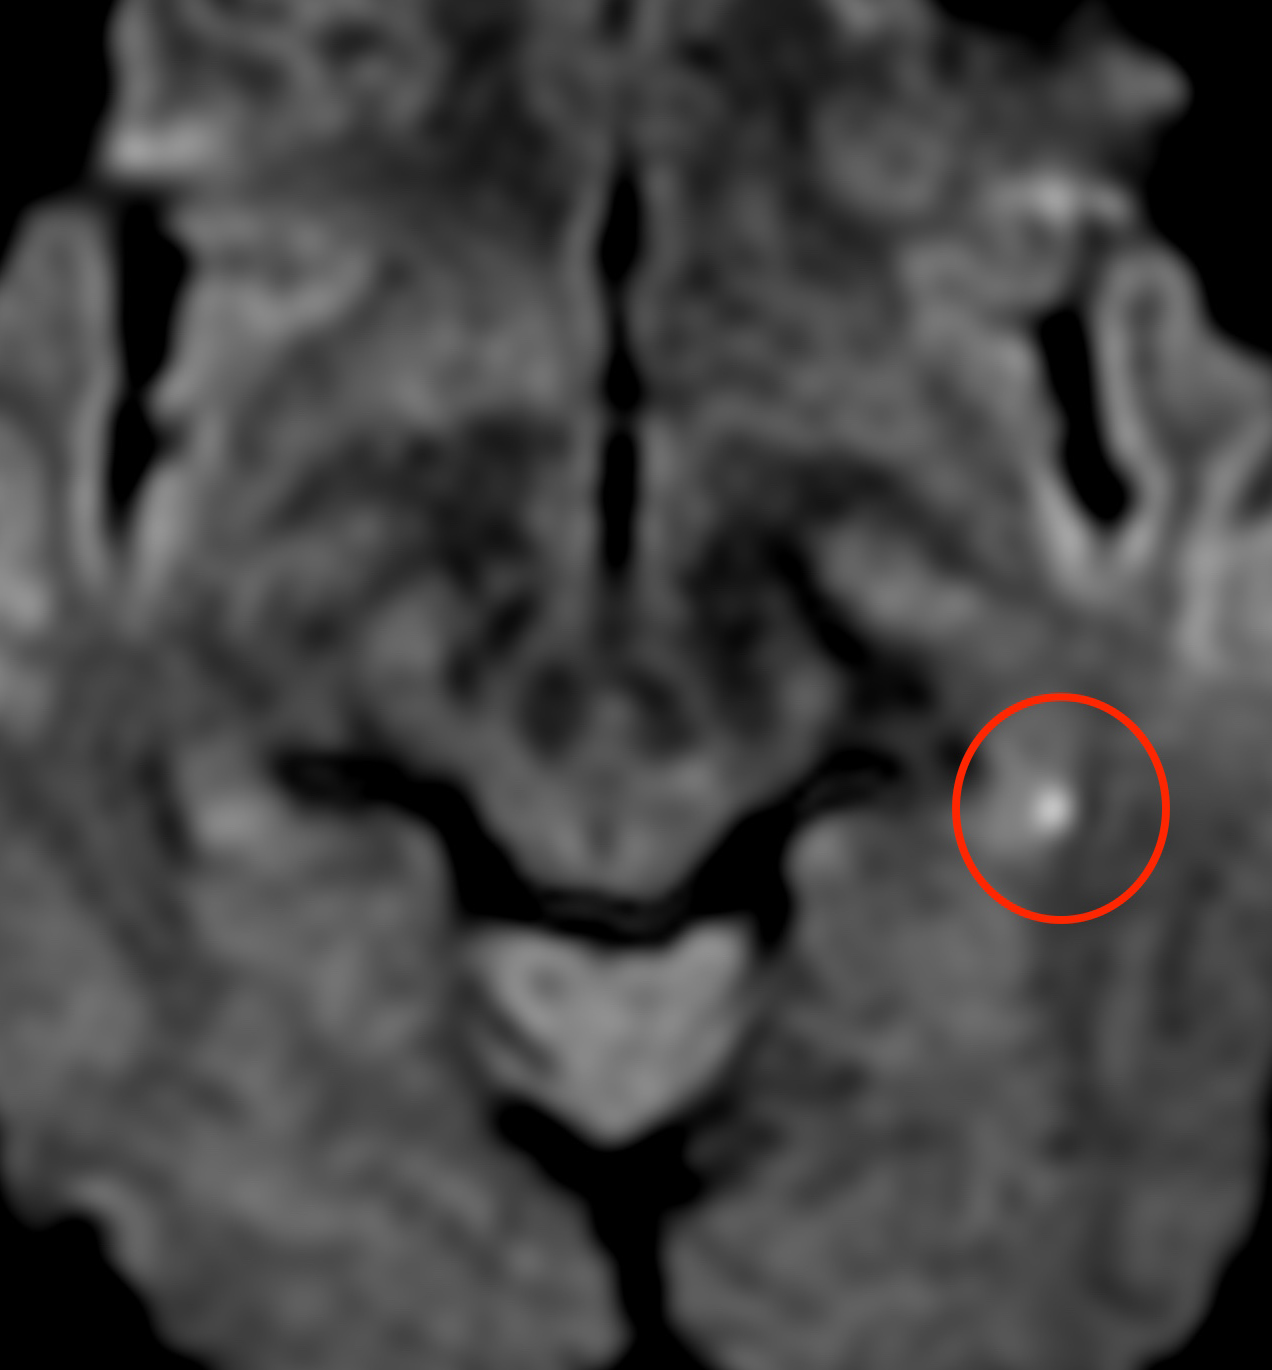

MRI検査(拡散強調画像)を確認すると、

右の海馬に白く光っている部分があり、症例1の方とは反対側ですが、やはり微小な脳梗塞と診断しました。

やはり症状からは一過性全健忘と診断されますが、実際には海馬の脳梗塞が原因という事になります。